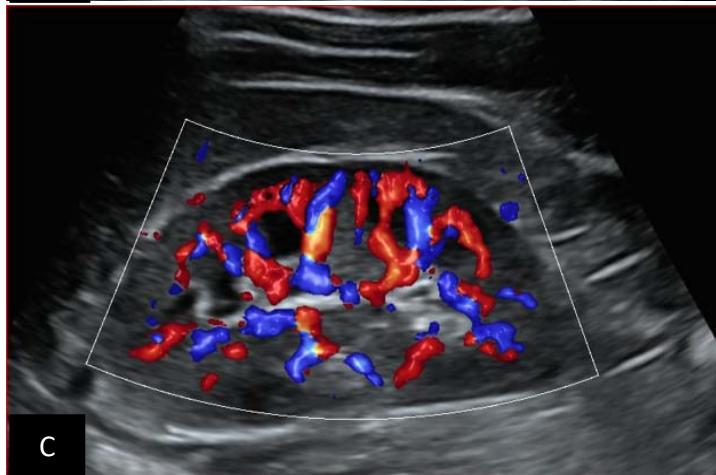

Figure 7: 7-year-old patient with normal renal Doppler ultrasound examination: Images A and B: normal morphology of the right kidney in B-mode; Image C: normal vascularization of the right kidney in color Doppler mode. Images C and D: represent a normal morphology of the left kidney in B mode. Image F: represents normal vascularization of the left kidney in color Doppler mode. Source: Dr. Frederick Tshibasu Tshienda database.